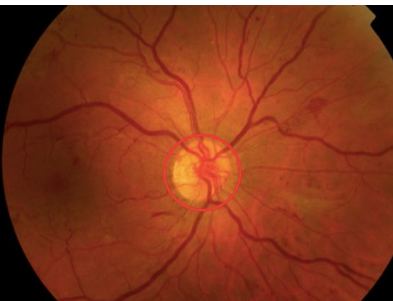

10

Q

Describe what is happening in this image [1]

A

Proliferative diabetic retinopathy: NVD new vessels on the optic disc

How well did you know this?

What treatment is suggested for this pathology? [1]

**Laser photocoagulation therapy is performed to stop the growth of new blood vessels.** *The white circular lesions represent focal laser surgery for proliferative diabetic retinopathy. Cotton wool spots, microhaemorrhages and neovascularisation can be seen across the remaining retina.*